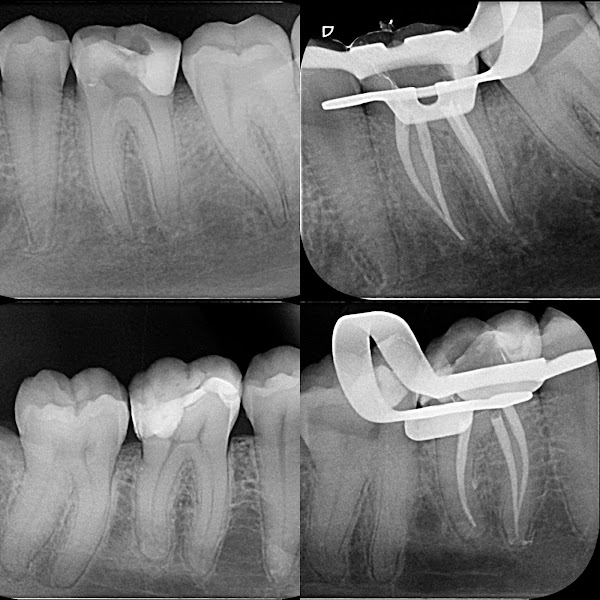

“Precisei de retratamento de canal porque, infelizmente, um dentista anterior não havia identificado que meu molar superior possuía 4 canais — tratou apenas 3. O atendimento com o Leonardo Schamann foi técnico, preciso e muito cuidadoso. Tive meu problema resolvido com competência. Recomendo com confiança!”